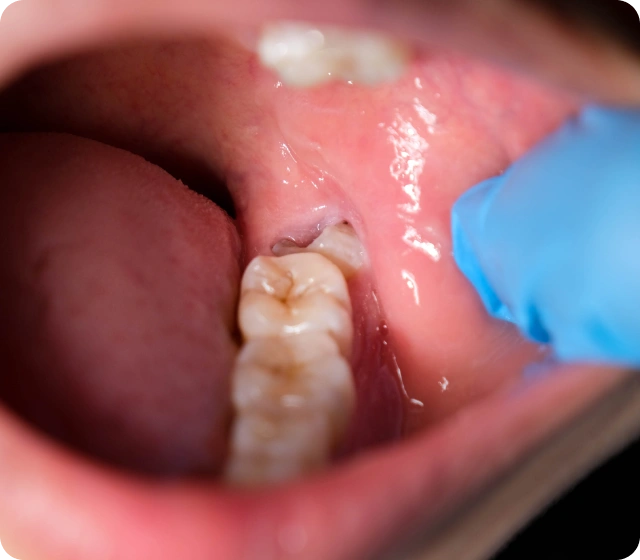

Bei den meisten Patienten wachsen die Weisheitszähne allerdings ungünstig und schief heraus, sodass es im Bereich der Weisheitszähne zu einer erhöhten Bakterienansammlung kommt und der Nachbarzahn geschädigt wird. Ebenfalls kann sich das Zahnfleisch bei einem erschwerten Durchbruch der Weisheitszähne entzünden. In solchen Situationen empfehlen wir Ihnen, sich die Weisheitszähne operativ bei uns entfernen zu lassen. Dies passiert auf Wunsch des Patienten unter Vollnarkose oder in einem Dämmerschlaf. Rufen Sie uns an! Unsere Patienten fragten auch: